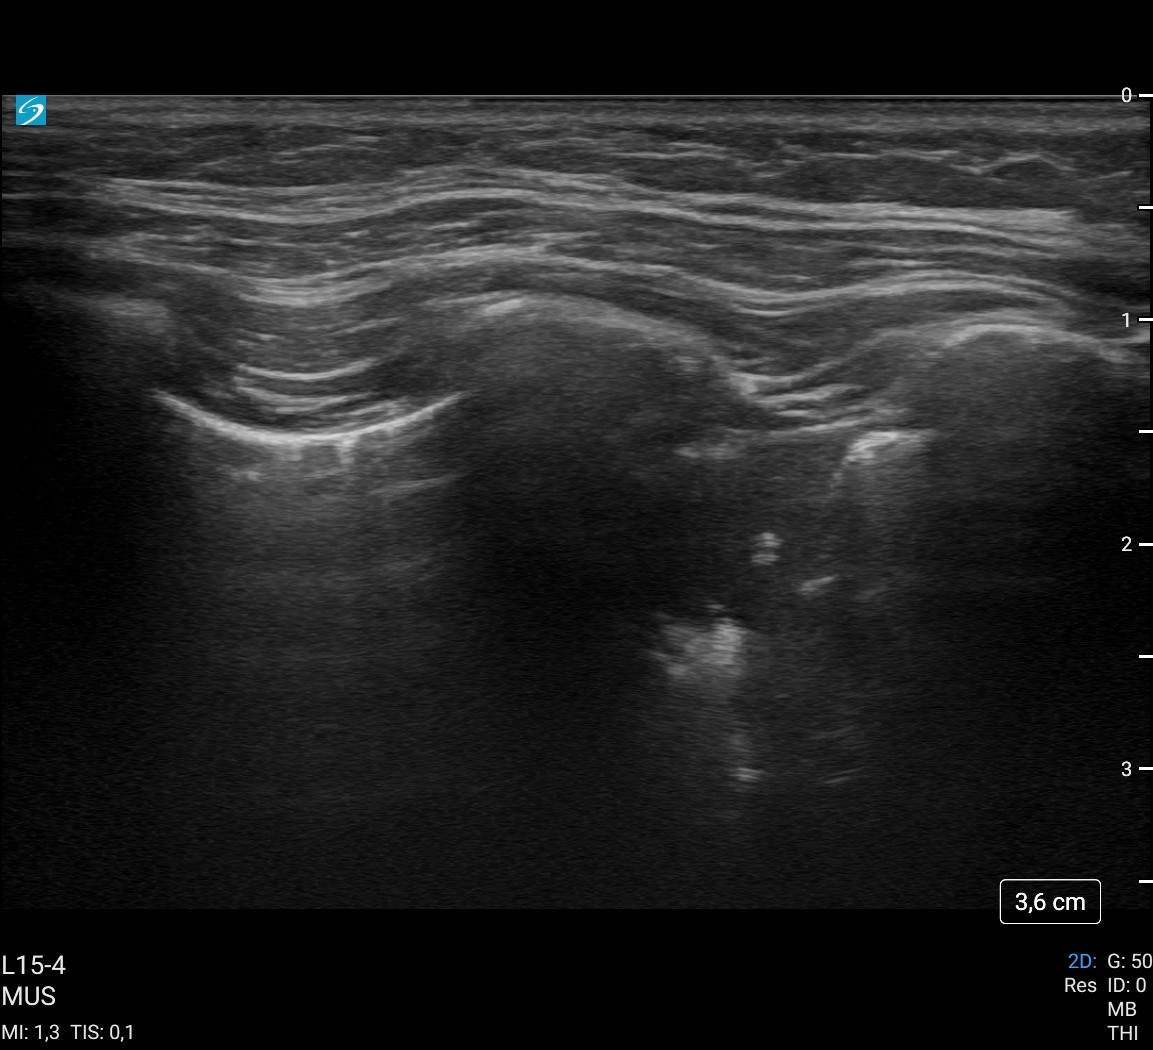

A la exploración física temperatura de 38 ºC, resto de constantes en rango. ORL sin alteraciones. A la auscultación pulmonar, presenta crepitantes en base derecha, por lo que realizamos ecografía pulmonar a pie de cama evitando así radiar a la paciente en una segunda ocasión.

Hallazgos ecográficos

Se objetiva consolidación pulmonar en lóbulo inferior derecho sin derrame asociado.